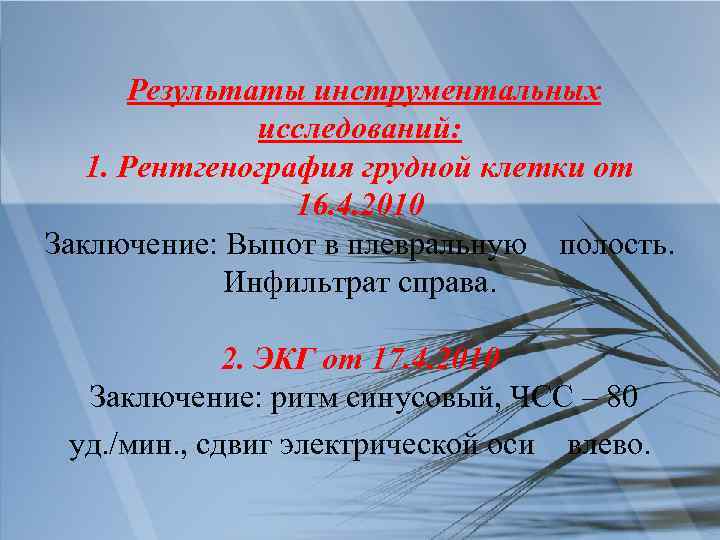

Инструментальные исследования: 1. Рентгенография грудной клетки в 2 -х проекциях. Позволит по форме затемнения уточнить диагноз пневмонии, оценить корни легких и не пораженную ткань легкого. 2. Фибробронхоскопия. Назначаем для выявления заинтересованности трахеи и главных бронхов в патологическом процессе. 3. ЭКГ

Результаты инструментальных исследований: 1. Рентгенография грудной клетки от 16. 4. 2010 Заключение: Выпот в плевральную полость. Инфильтрат справа. 2. ЭКГ от 17. 4. 2010 Заключение: ритм синусовый, ЧСС – 80 уд. /мин. , сдвиг электрической оси влево.